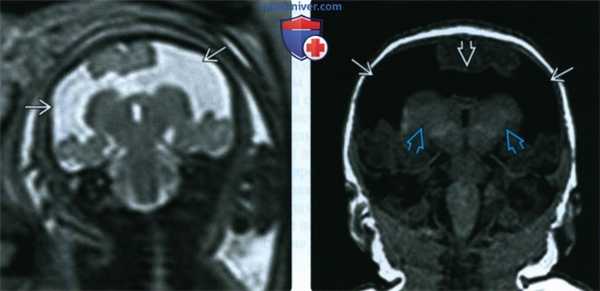

(Слева) При МРТ плода визуализируются крупные двусторонние дефекты, характерные для гигантской открытой шизэнцефалии.

(Справа) При исследовании в постнатальном периоде подтверждается наличие гигантских открытых дефектов и отсутствие ППП. Также заметна микроцефалия. Обратите внимание, что доли таламуса не сливаются, как это бывает при алобарной ГПЭ. Двусторонние дефекты, особенно таких размеров, всегда вызывают тяжелые неврологические нарушения.